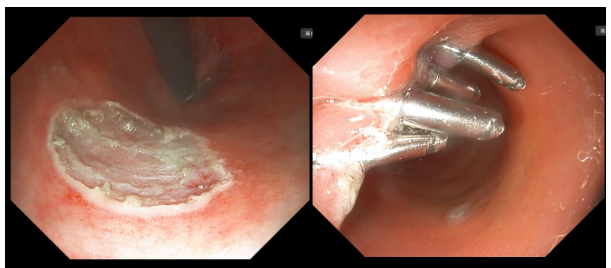

电子内镜:英美达双焦放大内镜 iPS-8100 max

内镜下:直肠可见一大小约0.6cm*0.6cm隆起型病变。

退镜观察,所见结肠粘膜表面光滑、润泽、血管网清晰,皱襞规则出现,部分粘膜粗糙,可见大片粘膜呈黄斑样改变,未见异常分泌物、糜烂、溃疡及肿物。直肠可见一大小约0.6cm×0.6cm息肉样隆起,予以粘膜下注射后抬举尚可,以圈套器圈套困难,故以圈套器尖端为针刀行粘膜切开后逐层剥离病变,术后创面封闭钛夹4枚止血,术后标本送检。